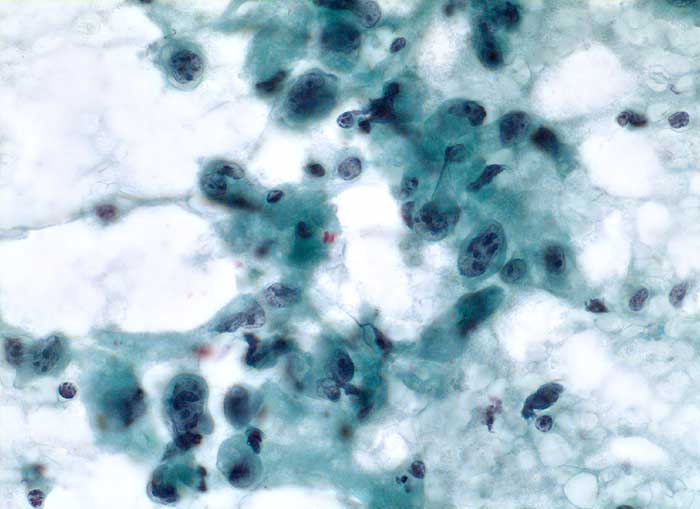

PathoPic – image database / PathoPic ID 5459 - Anaplastisches Schilddrüsenkarzinom

Anaplastisches Schilddrüsenkarzinom

Feinnadelpunktion Schilddrüse: Der Ausstrich enthält atypische Zellen, welche wesentlich grösser sind als regelrechte Schilddrüsenepithelien. Die Tumorzellen sind ein oder mehrkernig. Die Kerne sind stark polymorph, grob strukturiert mit meist mehreren plumpen Nukleolen. Das Zytoplasma ist unterschiedlich breit.

Strumaknoten links mit Einengung der Trachea

Zytologie

400